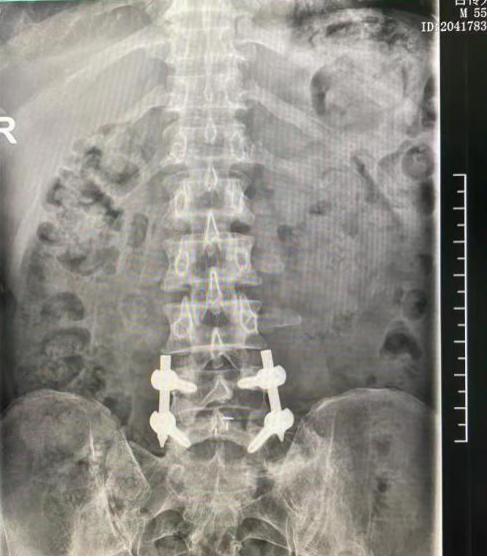

术后复查,内固定位置良好随着腰椎退行性疾病的发生率逐年上升,腰椎间盘突出症是临床上最常见的腰椎疾病,总体发病率在15%左右,中青年和老年人是腰椎间盘突出症的高发人群。经过系统保守治疗无效的患者往往需要手术治疗。由于大多数患者惧怕“开刀”,对微创手术需求不断增加,随着器械设备的不断改进与技术的逐渐成熟,使微创手术成为可能。张海龙主任医师所做的“微创”脊柱内镜腰椎椎间融合术(以下简称 “镜下融合”)采用的是经关节突入路镜下融合,配合熟练应用单及双通道进行微创脊柱融合的操作手术,该项新技术要求主刀医生要有丰富的临床经验和熟练的内镜下减压手术经验,配合先进的设备研发及不断地技术更新,才能被成熟应用在临床。